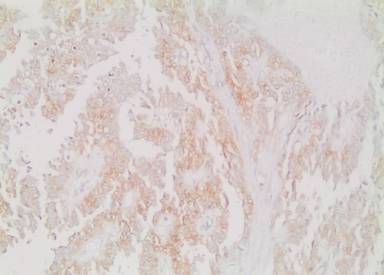

The pathological investigation showed a 13x12x11 cm pancreatic tumor, demarcated by a fibrous capsule and partial infiltration of fat tissue. Gross pathomorphology of the cut surface showed an inhomogeneous solid appearance with areas of bleeding and extensive calcifications. Microscopically, characteristic pseudopapillary formations were frequently observed (Figure 3). Pseudopapillae were formed when neoplastic cells drop away, leaving a variable number of cells surrounding delicate capillary-sized blood vessels. Immunohistochemistry was uniformly positive for vimentin (Figure 4) and CD 56 (Figure 5). Focal reactivity was detected for synaptophysin while negative reactions were found for chromogranin, neuron-specific enolase, CD10 and progesterone receptors. Proliferation index of Ki-67 was 1-2%. On the basis of these characteristic morphologic and immunohistochemical findings, the diagnosis of locally invasive solid pseudopapillary tumor of the pancreas was made. The pathologic investigation showed positive pancreatic resection margin for the tumor. For that reason re-resection of the pancreas was decided on a second look surgery. On April 2012 laparotomy was done and near total pancreatectomy was performed. The pathologic investigation for the second specimen showed negative pancreatic resection margin for tumor.

Figure 4. Tumor cells showing immunopositivity for vimentin. |